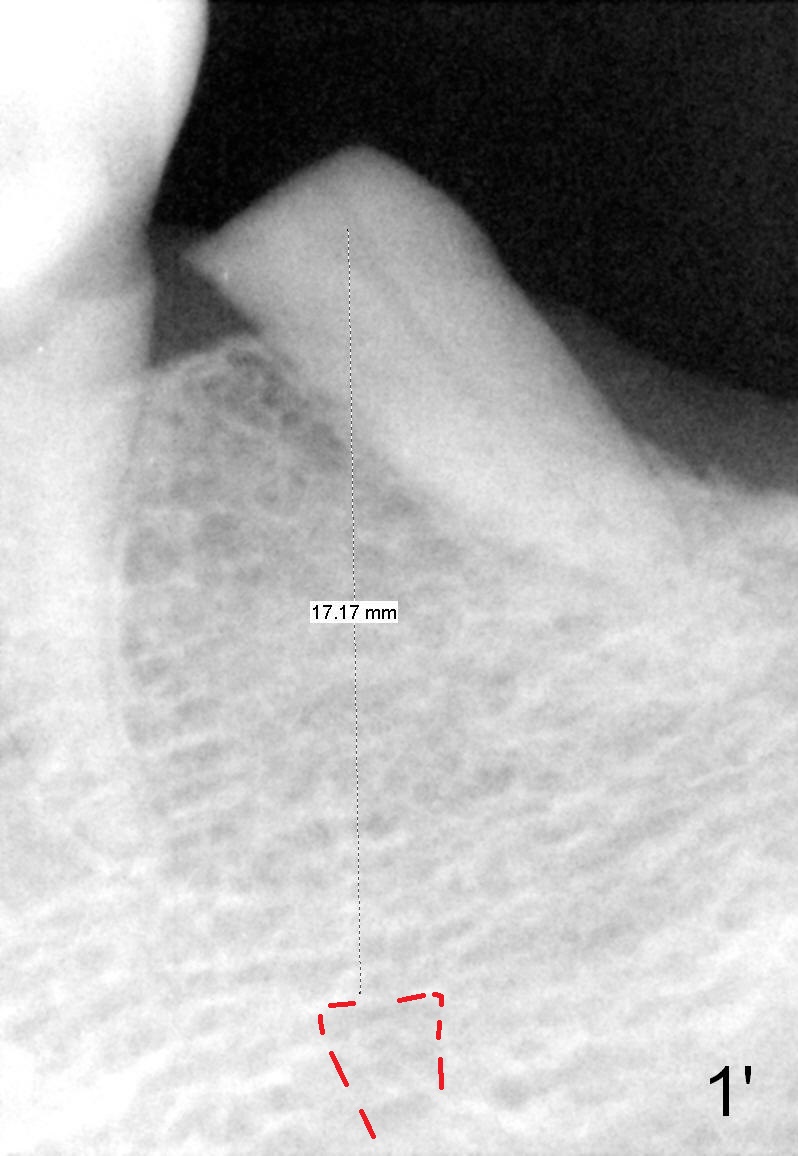

A 78-year-old lady is scared of dentistry, but she has no problem having a 2nd immediate implant (#20 in Fig.1) once the 1st one turns out to be without pain. The challenge associated with #20 is its long axis. After extraction, the osteotomy is initiated in the mesial socket wall at the junction of the upper and middle 1/3 obliquely (Fig.2, slightly lingually). Once the entry is obtained, the axis of the pilot drill is changed to be parallel to the neighboring tooth (Fig.3); an implant spacer of 2.5 mm is used to check (against the 2 mm pilot drill) so that the center of the osteotomy is 3.5 mm from the neighboring tooth (Fig.4). The implant will be 4.5x14 mm. The depth is not longer than that of the neighboring tooth so that it should be quite safe relative to the Mental Loop and the Inferior Alveolar Canal (yellow dashed line in Fig.1). The apical socket is packed with collagen dressing while the coronal one with bone graft. An immediate provisional will be fabricated to keep the graft in place. The osteotomy should be as lingual as possible to avoid the Mental Loop (Fig.1' red dashed line).